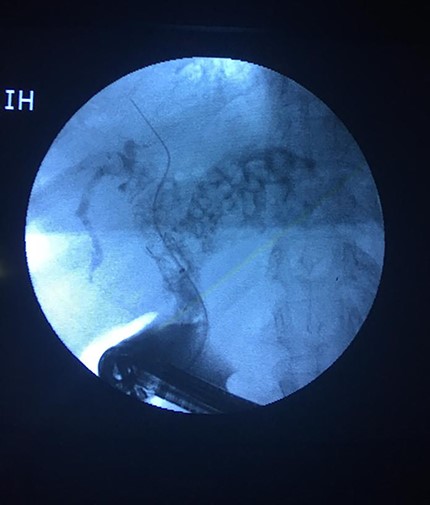

We present a 79-years-old female patient who presented on the 31 January 2019 with worsening recurrent right upper quadrant pain, dark urine, chills and tiredness for 12 months. She was a known diabetic and hypertensive controlled on medications. Her past surgical history was notable for having had an open cholecystectomy for symptomatic cholelithiasis in 2016. The same year post cholecystectomy, she was found to have retained common bile duct (CBD) stones. She had endoscopic retrograde cholangiopancreatography (ERCP), during which a complete clearance of the stone was not achieved and she was stented with a completely covered metal stent. There was no follow-up until she got symptomatic in 2019 and she presented with cholangitis. Her blood workup showed an obstructive picture. The abdominal ultrasound was not diagnostic. She was started on analgesia and antibiotics. A differential diagnosis of a blocked stent was made. She had an ERCP on the 04 February 2019. An old stent was found, which could not come out. An extraction balloon was used to clean the old stent of debris and small stones and a 10 Fr × 9 cm plastic stent was deployed. On table, cholangiogram showed dilated ducts with multiple stones in the CBD extending into the left and right hepatic ducts and the first order ducts bilaterally (Fig. 1). MRCP confirmed the cholangiogram findings (Fig. 2). On 18 February 2019, she had open bile duct exploration and Roux-en-Y hepaticojejunostomy reconstruction (wide anastomosis). The stents and multiple stones were removed (Fig. 3). She had an uneventful post-operative course. At her first follow-up, 6 weeks later, she had normal liver function tests and felt much better.